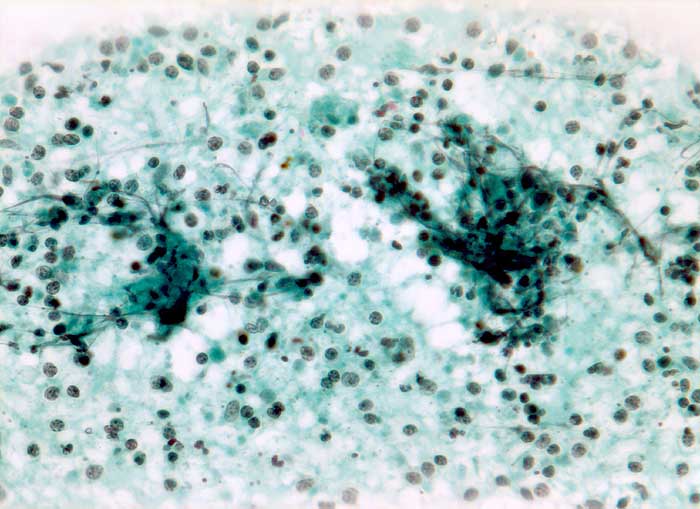

p/ Tuberkulöse Lymphadenitis

Tuberkulöse Lymphadenitis

Die meist atrophischen Epitheloidzellen sind oft nur schwer von Venulenendothelien unterscheidbar und sind nur relativ selten zu deutlich erkennbaren Granulomen zusammengeballt. Bei Vorliegen von verkäsenden Granulomen erscheint der Ausstrich feinkörnig-detritisch. Eine granulozytäre Entzündung muss bei AIDS Patienten an eine Tuberkulose denken lassen.

Die Ziehl-Neelsen Färbung zum Nachweis der säurefesten Stäbchen kann nachträglich am Pap-gefärbten Präparat durchgeführt werden.